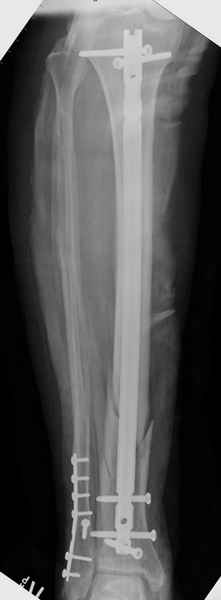

Здесь мы использовали новый Synthes Nail с дополнительными дырками, в проксимальной части 4: по две косых и поперечные (один стандартный а другой динамический), в дистальной части две поперечные, прямая и косая. Вес больного более 120 кг, нагрузку начнем через месяц.